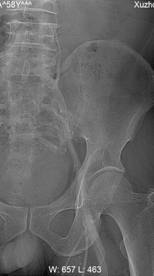

朱××,男,45岁,双侧股骨头坏死,左侧髋关节疼痛明显,不能独立行走,需使用止痛药物(图1,MR)。介入治疗术中造影(图2a)示:股骨头供血动脉分支稀疏,远端痉挛、股骨头骨质内无明显分支动脉血管;治疗后(图2b)造影见股骨头供血动脉分支血管明显增多,远端可见达股骨头骨质内,原髋关节疼痛消失,自行行走出院。

何××,男,6岁,儿童股骨头坏死,左侧股骨头骨骺坏死、骨质碎裂(图3),经治疗后骨骺骨质恢复(图4)。